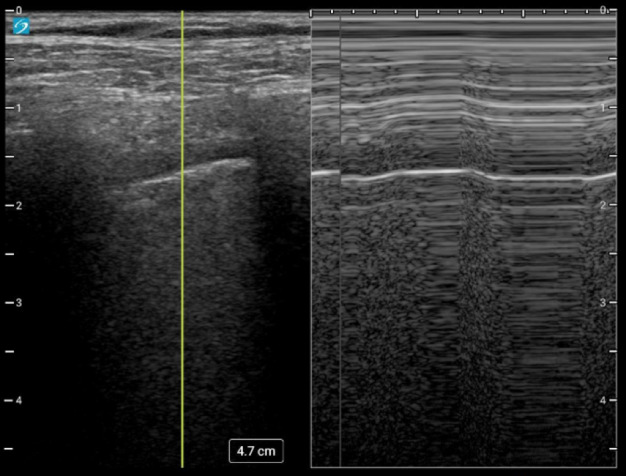

Point of Care Ultrasound (POCUS) is used to evaluate many clinical scenarios. Chest POCUS has been integrated as a part of a clinical protocol to assess patients with lung pathology 1. The ability to detect pneumothorax using chest POCUS has been shown to be superior to chest radiography, with specificity reported to be as high as 100% when a lung point sign is identified. In addition to improved diagnostic accuracy, chest POCUS has the added benefits of ease of access and absence of ionizing radiation. Here we describe a case where a patient with a high pre-test probability for pneumothorax had a detected lung point sign, but pneumothorax was ruled out via Computed Tomography (CT). This case highlights the importance of considering the mimics of the lung point sign. This case also shows a unique and interesting finding related to pleural movement restriction post-Bronchoscopic lung volume reduction (BLVR).